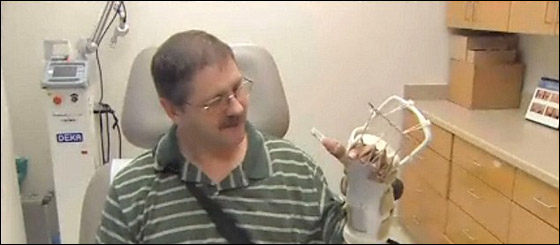

والآن يستخدم ريد، الذي يعيش بجيلمر شرق دالاس، جبيرة من نوع خاص ساعدته على استعادة شيء من الإحساس في ذراعه. ويقول ريد: "عندما دخلت غرفة العمليات وخرجت لم أتوقع أن أجد يدي. كنت سعيدًا عندما رأيتها.. وبمجرد أن ارتديت هذه الدعامة وشعرت بأني قادر على استخدامها وأنا أخطط لحمل أحفادي مرة أخرى".

ويعرب عن إعجابه بالعملية الجراحية قائلا: "نحن نعتبر هؤلاء الأطباء معجزة. لقد قاموا بمهمة مدهشة. أنا فعلاً محظوظ لأني بقيت حيًا حتى الآن". ومن جانبه، يقول دكتور سوميت تيوتي، أستاذ جراحة التجميل الذي جاء للمشاركة في العملية: "إن دكتور أميرلاك فعل شيئًا القسم بكامله لم يسمع عنه من قبل. كل ما أستطيع أن أقوله إن هذا شيء رائع. الذراع كانت مكسورة بشكل كامل".